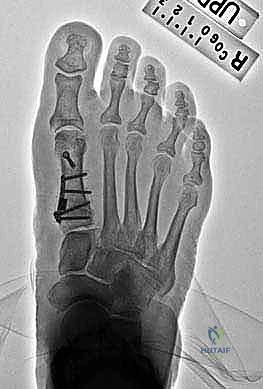

Image

Site and position of first metatarsal opening wedge osteotomy. The osteotomy is initiated about 1.5 cm distal medial to the first MTC joint.